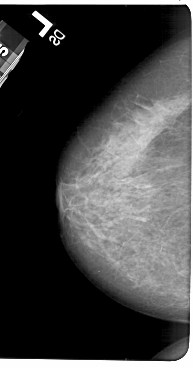

A_1602_1.LEFT_MLO

LEFT_MLO LINES 5491 PIXELS_PER_LINE 2761 BITS_PER_PIXEL 12 RESOLUTION 43.5 NON_OVERLAY